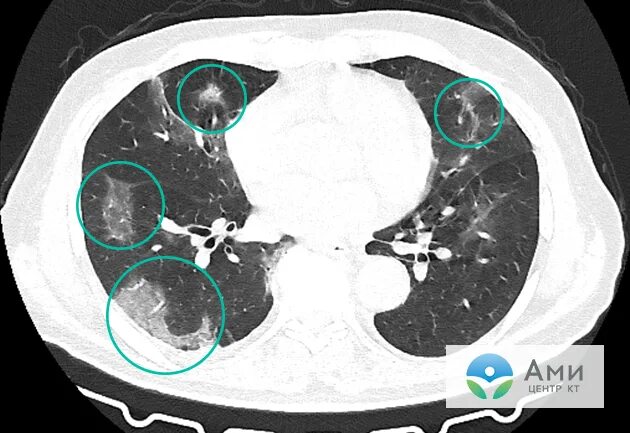

Скате легких